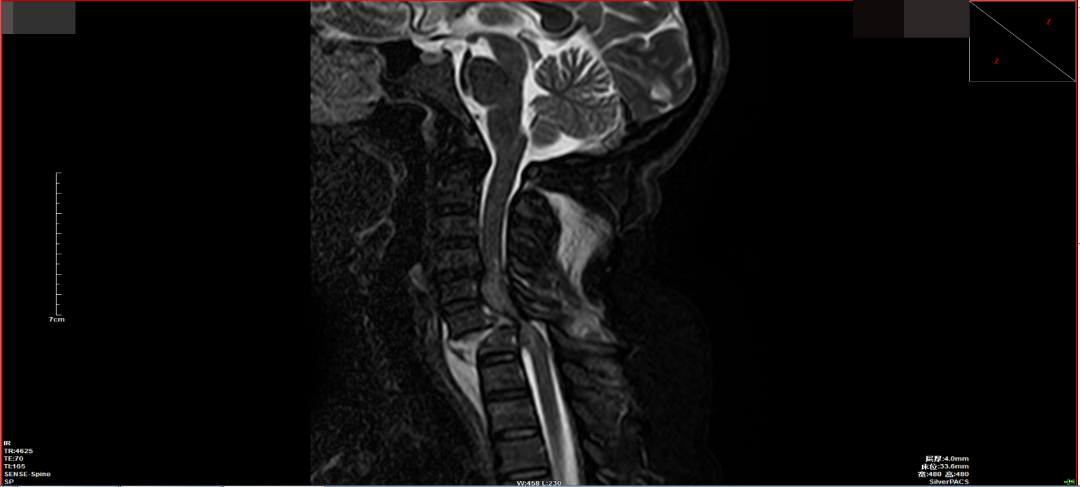

脊柱外科值班醫師接診病人後(hòu)診斷羅阿姨是頸椎骨折脫位并脊髓損傷,合并四肢癱,随後(hòu)醫師爲患者行顱骨牽引治療。針對(duì)羅阿姨的情況,脊柱外科團隊進(jìn)行讨論後(hòu)一緻認爲患者目前四肢肌力0級,胸骨角平面(miàn)以下感覺喪失,鑒于脊髓損傷恢複難度大,卧床并發(fā)症多,最佳治療措施是行頸椎骨折脫位切開(kāi)複位椎弓根螺釘内固定+椎闆切除椎管擴大減壓術。

經(jīng)脊柱外科醫護團隊精心的圍術期準備,在麻醉科的密切配合下,羅阿姨的手術得以順利實施。術後(hòu)第二天,羅阿姨脊髓損傷症狀有較明顯好(hǎo)轉,雙上肢已可擡離床面(miàn),肌力4級,感覺障礙平面(miàn)下降至劍突水平。預計在後(hòu)續的康複治療中,及時(shí)有效的手術減壓固定能(néng)爲患者提供更好(hǎo)的頸椎穩定性,挽救更多的脊髓組織,最大程度的恢複脊髓神經(jīng)功能(néng)。

脊柱外科負責人李建軍表示,頸椎椎弓根釘棒内固定術是頸椎骨折脫位治療中技術難度最大、手術風險最高的手術之一。頸椎解剖複雜精細,其椎弓根直徑最窄處僅爲3mm。頸椎椎弓根内側有頸髓向(xiàng)下走行,椎弓根外側椎動脈穿過(guò),因此其置釘難度非常大。手術中必須保證椎弓根螺釘置釘精準,突破外側皮質可導緻椎動脈和神經(jīng)根損傷,突破内側皮質可侵入椎管,造成(chéng)脊髓損傷,極其考驗手術團隊的技術能(néng)力。